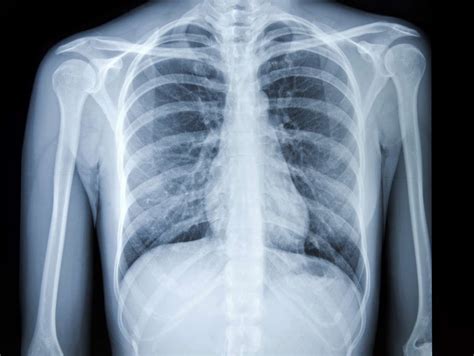

Normal Chest X-ray in Acute Bronchitis

A normal chest X-ray in a patient presenting with acute bronchitis symptoms is a common finding. This indicates that the inflammation is primarily limited to the airways and hasn’t significantly affected the lung tissue.

The absence of abnormalities on the X-ray helps confirm the diagnosis of acute bronchitis and rule out other conditions like pneumonia.

A normal X-ray finding can reassure patients and guide appropriate treatment strategies for acute bronchitis.

A normal chest X-ray typically shows clear lung fields with no evidence of consolidation, masses, or pleural effusions. The airways appear normal, and the diaphragm is well-defined.

The ribs, heart, and major blood vessels are also clearly visible without any abnormalities.

A normal chest X-ray suggests the absence of significant lung disease.